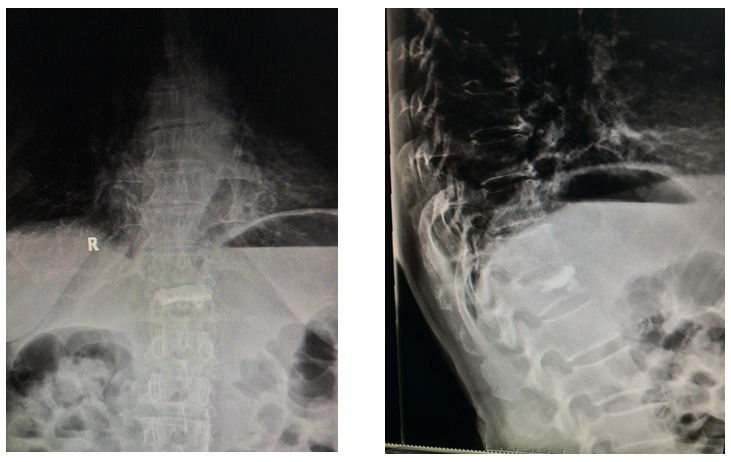

术后3月X光

•      术后3月CT

术后X线

术前后侧位